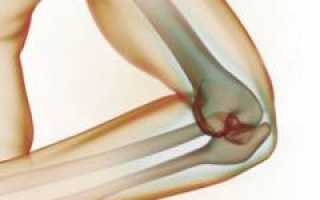

Локтевой сустав

Локтевой сустав — один из самых сложных в организме из-за своей структуры. Он образован тремя костями: плечевой, лучевой и локтевой. Плечевая кость находится между плечом и локтем, а лучевая и локтевая кости составляют предплечье, располагаясь параллельно: лучевая — снаружи, локтевая — внутри.

Локтевой сустав формируется соединением двух костей предплечья и одной плечевой. Его сложность заключается в наличии мелких суставов: плечелучевого, плечелоктевого и лучелоктевого, которые образуются за счет соединения этих костей.

В состав локтевого сустава входят:

- плечелоктевой сустав;

- плечелучевой сустав;

- проксимальный (верхний) лучелоктевой сустав.

Все три сустава (плечелучевой, плечелоктевой и лучелоктевой) взаимодействуют и покрыты общей суставной капсулой из соединительной ткани. Внутренний слой — синовиальная оболочка, вырабатывающая жидкость для смазки суставных поверхностей. Два наружных слоя состоят из плотных соединительных тканей, выполняющих защитную функцию.

Суставная капсула обволакивает концы костей, входящих в локтевой сустав. Верхние концы прикрепляются к плечевой кости, а нижние — к локтевой и лучевой, обеспечивая полное покрытие суставных поверхностей.